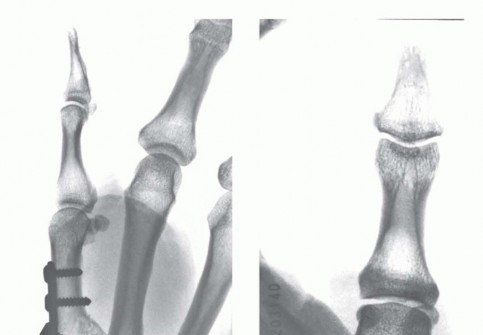

Open Reduction and Internal Fixation (ORIF) - Wagner Approach

For fractures with large volar-ulnar fragments (>20% of the articular surface), displaced Rolando fractures, or cases where closed reduction fails, ORIF is unequivocally mandated. The classic Wagner approach provides unparalleled exposure to the thumb CMC joint. A curvilinear incision is made along the glabrous border of the thenar eminence, curving dorsally at the level of the CMC joint.

For a large fragment Bennett fracture, the shaft is reduced to the volar-ulnar fragment using a pointed reduction clamp. Provisional fixation is achieved with a K-wire. A 1.5mm or 2.0mm lag screw is then placed perpendicular to the fracture plane. The near cortex must be overdrilled (gliding hole) and the far cortex underdrilled (thread hole) to achieve true interfragmentary compression. The screw head should be countersunk to prevent hardware prominence beneath the thenar muscles.

Image